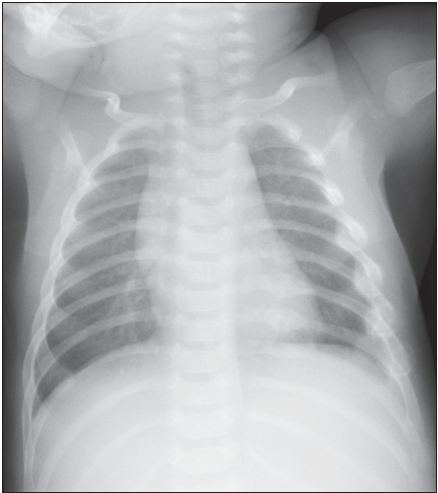

Radiographic studies, including a skeletal survey and brain CT, were ordered. The skeletal survey (Figure) demonstrated healing posterior fractures of the left sixth through eighth ribs and lateral rib fractures of the left fourth through seventh ribs. A CT scan of the head was normal. Ophthalmologic examination revealed left lateral subconjunctival hemorrhage. Retinal hemorrhages were not present.

Rib fractures in an infant are a major indicator of physical abuse. A study of 39 infants with rib fractures found that 82% had been physically abused.2 Other, much less common mechanisms of injury were serious accidents, birth trauma, or conditions of bony fragility. Because rib fractures in infants were usually the result of abuse, the authors recommended thorough clinical and radiologic evaluation. Posterior rib fractures are especially suggestive of physical abuse. Most rib fractures, particularly posterior rib fractures, are attributed to violent shaking (as opposed to direct impact of chest compression).3